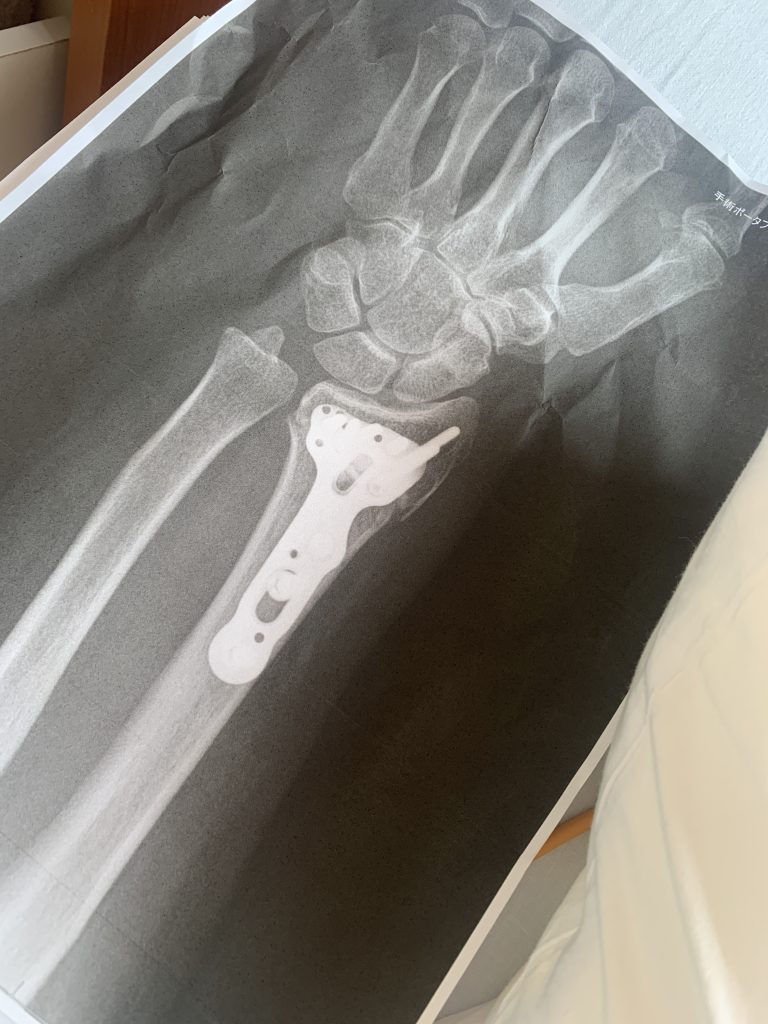

6月には、生まれて初めて骨折をして、一時はとても大変でしたが、今はなんとか動くようになり普通に日常生活を送ることができてます。左手首とは言えとても不自由でした。

8月位には自転車も乗れるようになり、仕事も少しずつ始めました。